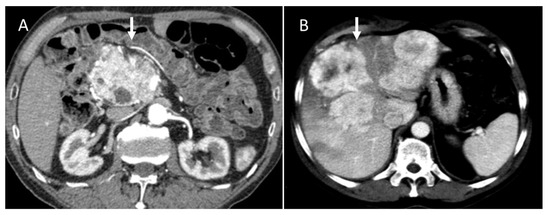

The main prognostic factors for GEP-NETs are the primary site, with a poorer prognosis in the pancreatic location (PNET) (Figure 3); the TNM stage; and the histopathological classification according to the World Health Organization (WHO), which includes the morphological and proliferative criteria based on the Ki67 index [1]. An additional positive prognostic factor is the expression of the somatostatin receptor, which is the basis of imaging diagnosis on Gallium-68 DOTA-TATE Positron Emission Tomography/Computed Tomography (PET/CT) and somatostatin analog (SSA) therapy, including octreotide acetate and peptide receptor radionuclide therapy (PRRT) (such as lutetium Lu 177 dotatate) [6,7].

Figure 3.

CT evaluation during arterial phase of pancreatic NEN ((A): arrow) with liver metastases ((B): arrow).